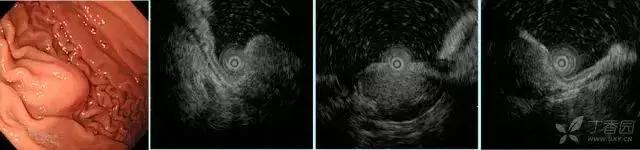

图 3胃平滑肌瘤。 A 胃体小弯可见黏膜下隆起;B EUS 下固有肌层可见圆形、均匀低密度回声;C-D HE 可见梭形细胞,免疫组织化学可见α-SMA(+)

图4 异位胰腺(浅型)。白光胃角可见脐样黏膜下隆起,超声内镜下可见黏膜肌层-黏膜下层有一界线不清之偏高回声病变

图5 胃体异位胰腺(深型)。白光下胃体大弯可见半球型黏膜下隆起,超声内镜下可见一界线模糊的偏高回声病变,起源于黏膜下—固有肌层,类似肌层增厚表现